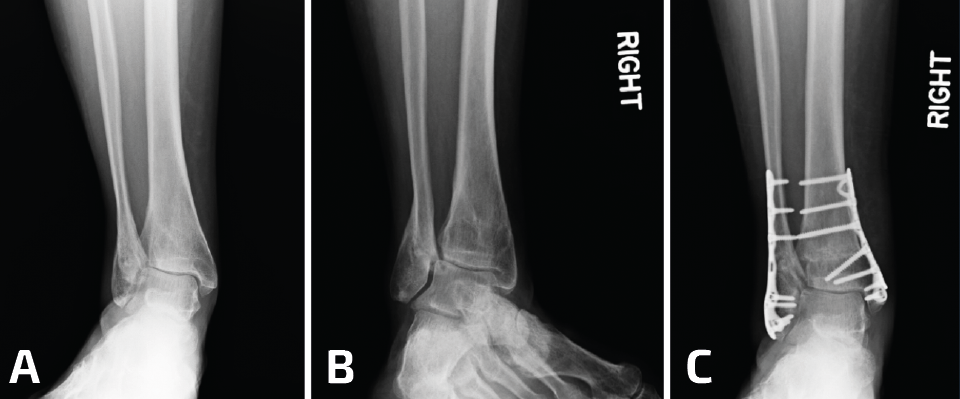

La selección de la osteotomía y el tipo de injerto para la reconstrucción va a depender de la posición de la mala consolidación; recuerden que el peroné puede estar acortado o rotado a externo, o bien acortado y rotado a interno. Idealmente, no sería necesario desprender la sindesmosis en su totalidad para elongar el peroné (Figura 3). Si el peroné está rotado hacia afuera y no está acortado, entonces se puede realizar una osteotomía rotacional sin elongación y, de esta manera, se preserva la sindesmosis, aunque esto no es una condición frecuente. El objetivo del tratamiento de la consolidación viciosa del peroné consiste en restaurar la correcta longitud y la rotación, para obtener una alineación anatómica del astrágalo dentro de la mortaja del tobillo. Sin embargo, también es importante reconocer otros aspectos del patrón original de la fractura.

Figura 3. En este paciente, además de la pseudoartrosis del peroné, se asocia un gran defecto osteocondral del astrágalo (A, B, C). Para acceder a la lesión, se realizó una osteotomía en la región lateral de la tibia (D, E, F). Después de la colocación de los injertos tomados de la rodilla, se realizó la osteosíntesis de la osteotomía de la tibia y posteriormente se trató la pseudoartrosis del peroné (G, H).